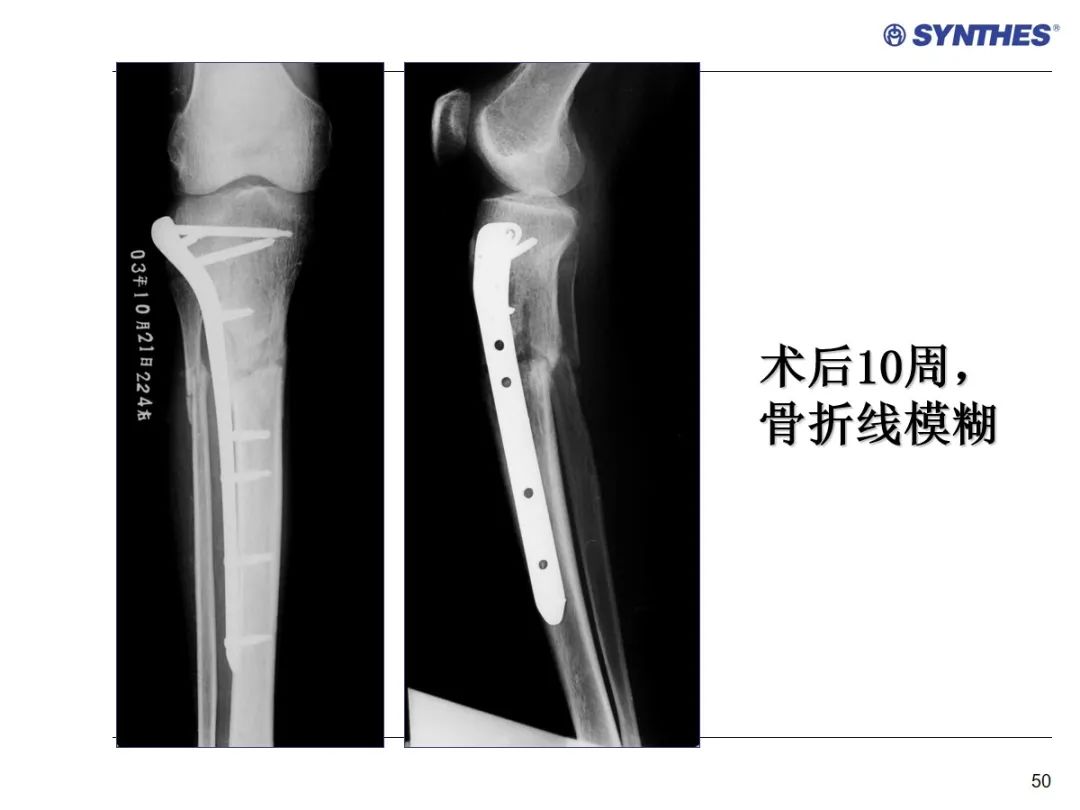

LISS微创固定系统应用技巧,原来如此简单!